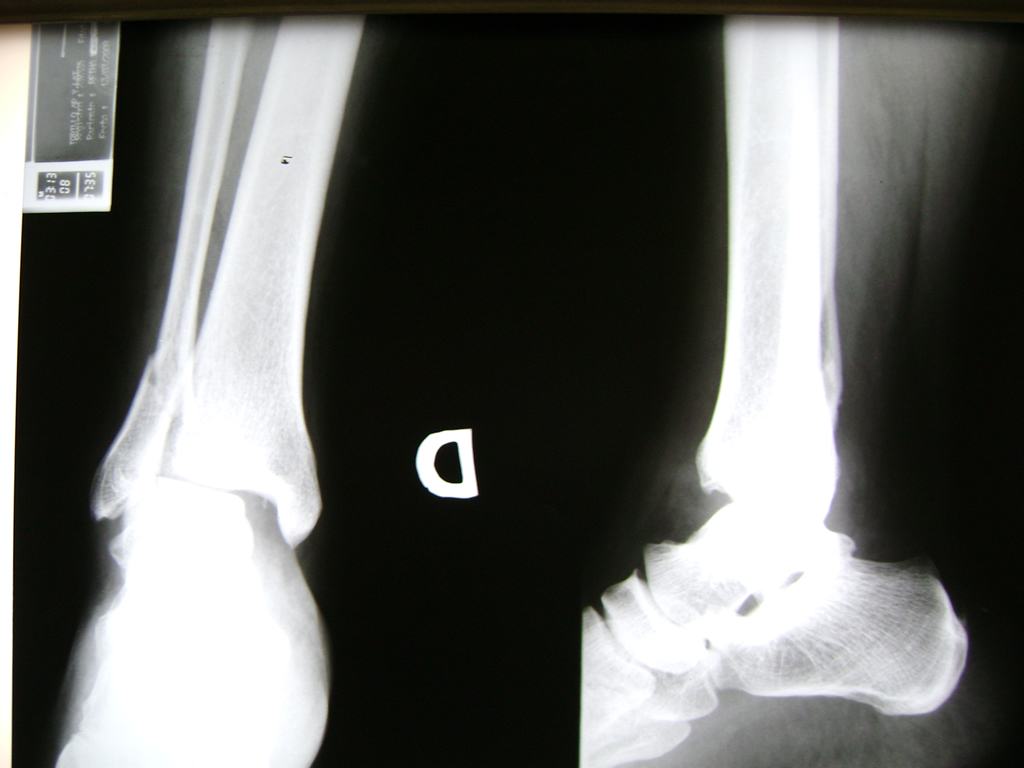

Una fractura de tobillo es la rotura de uno o más de los huesos del tobillo. Estas fracturas pueden ser:

- Parciales (el hueso está sólo parcialmente fisurado, no del todo).

- Completas (el hueso está perforado y está en 2 partes).

- Producirse en uno o ambos lados del tobillo.

Algunas fracturas de tobillo pueden requerir cirugía si:

- Los extremos de los huesos están desalineados entre sí (desplazados).

- La fractura se extiende hasta la articulación del tobillo (fractura intra-articular).

- Los tendones o ligamentos (tejidos que sujetan los músculos y los huesos entre sí) están rotos.

- El médico cree que sus huesos probablemente no sanen apropiadamente sin cirugía.

- El médico considera que la cirugía puede permitirle una recuperación más rápida y confiable.

- En los niños, la fractura involucra la parte del hueso del tobillo donde el hueso está creciendo.

Cuando se necesita cirugía, es probable que esta implique el uso de clavijas de metal, tornillos o placas para sostener los huesos en su lugar mientras la fractura se consolida. Los elementos de soporte pueden ser temporales o permanentes.